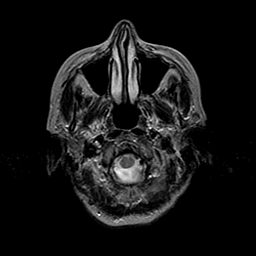

Metastatic Adenocarcinoma of the Colon: T2-weighted MR -- Slice #2

[Home][Help][Clinical] Slice 2